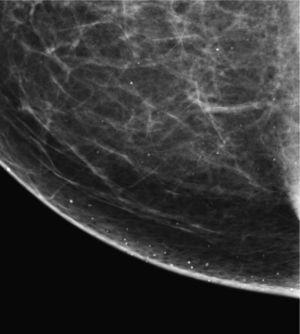

Necrosis grasa (fig. 3). La liberación de sustancias adiposas, causada por un traumatismo o intervención quirúrgica, puede provocar reacción inflamatoria y posteriormente calcificaciones distróficas de aspecto grosero y bordes irregulares2-6. Clínicamente puede presentarse como una masa indurada. La forma de presentación más típica son los quistes oleosos (fig. 4), que son lesiones radiotransparentes con calcificación periférica (en cáscara de huevo) secundaria a la calcificación de las paredes de los quistes.